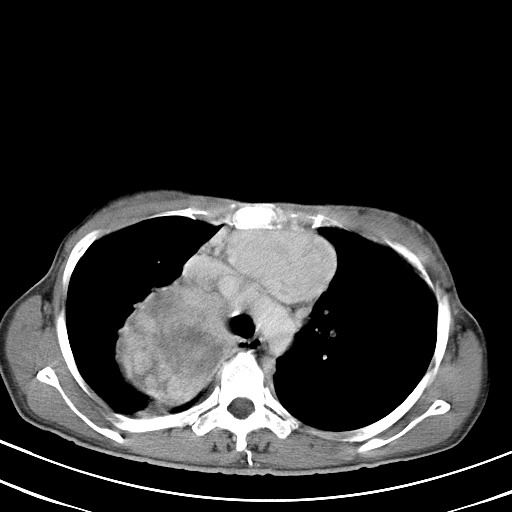

以下是引用汪涛同志在2007-8-2 0:40:00的发言:[br]病变虽然广泛,同时侵及双侧纵隔,但是无论左侧和右侧上下观察都是与右侧颈部甲状腺相延续的,而且强化幅度基本一致,又同时具有恶性病变病变的某些特征:肿块过大且密度不均,部分层面与正常纵隔结构分界不清,结合病史已有两年,考虑:胸内甲状腺肿恶变可能。[br]